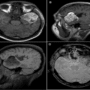

•T1 weighted axial (A) and sagittal (B) image showing an extra-axial hyperintense mass in the left middle cranial fossa. Tiny T1 hyperintense foci are seen in the subarachnoid space along the left convexity(disseminated fat droplets).

•T1 weighted fat saturated sagittal image (C) showing suppression of hyperintense areas confirming fat content

•T2 Gradient echo image (D) showing hypointense areas.